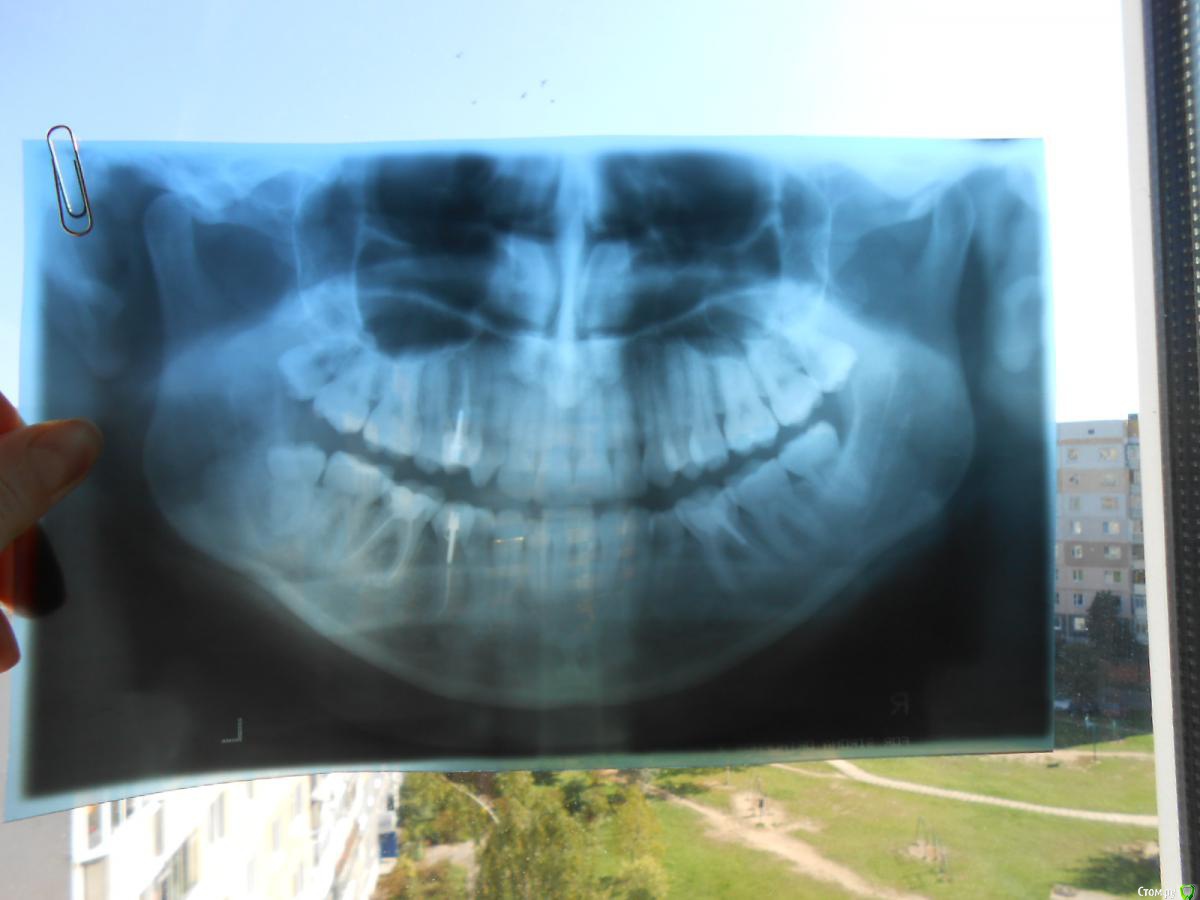

Ольга1991 Опубликовано 23 сентября, 2015 Поделиться Опубликовано 23 сентября, 2015 Здравствуйте, Уважаемые Доктора!Наконец-то решилась на удаление, но есть несколько вопросов.Надеюсь, Вы поможете мне с ними разобраться 1. Насколько сложным будет удаление 8-ого зуба (на снимке слева, нижний)? И есть ли смысл ложиться в стационар? 2. Что будет, если удалить сразу три "восьмёрки"? Практикуется ли такое вообще?(Понимаю, что приятного в данной процедуре мало, но мне проще один раз отмучиться, чем целых ТРИ!!!) 3. Возможно ли удаление под общим наркозом? Ссылка на комментарий

diesel87 Опубликовано 23 сентября, 2015 Поделиться Опубликовано 23 сентября, 2015 Мне кажется вы слишком утрируете. Мдаа, зуб не в кости, по снимку есть резорбция кости сзади коронки, рядовое удаление восьмерки. Если распилить, совсем просто будет. Ссылка на комментарий

Ольга1991 Опубликовано 23 сентября, 2015 Автор Поделиться Опубликовано 23 сентября, 2015 (изменено) Мне кажется вы слишком утрируете. Мдаа, зуб не в кости, по снимку есть резорбция кости сзади коронки, рядовое удаление восьмерки. Если распилить, совсем просто будет.Да, наверно я что-то не так поняла. Зуб не в кости, но проблема именно в ней, по словам врача. Возможно она имела в виду именно резорбцию. Я не специалист, терминов не знаю. Изменено 23 сентября, 2015 пользователем Ольга1991 Ссылка на комментарий